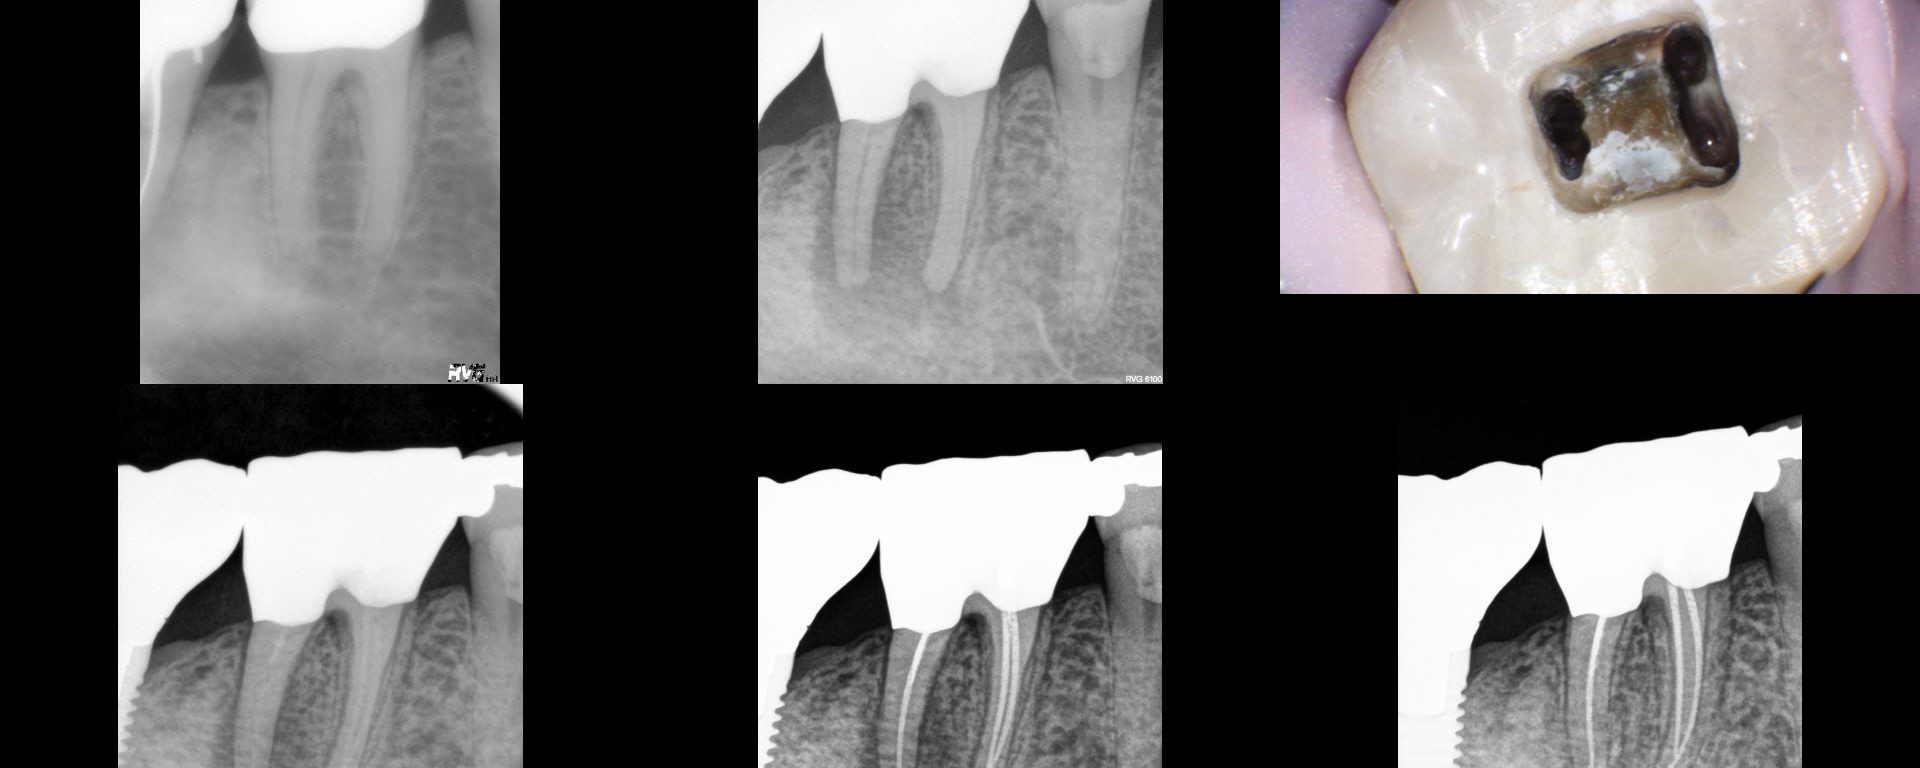

Nec/SAP. I had a historical on this from 2005…subsequent to which a Zirc was placed. I took a look at it and knew there wasn't going to be any point in a traditional access…i.e. even if I cut a traditional access, it would be a search and try-not-to-destroy in the roots.  Found four PONs. CBCT […]